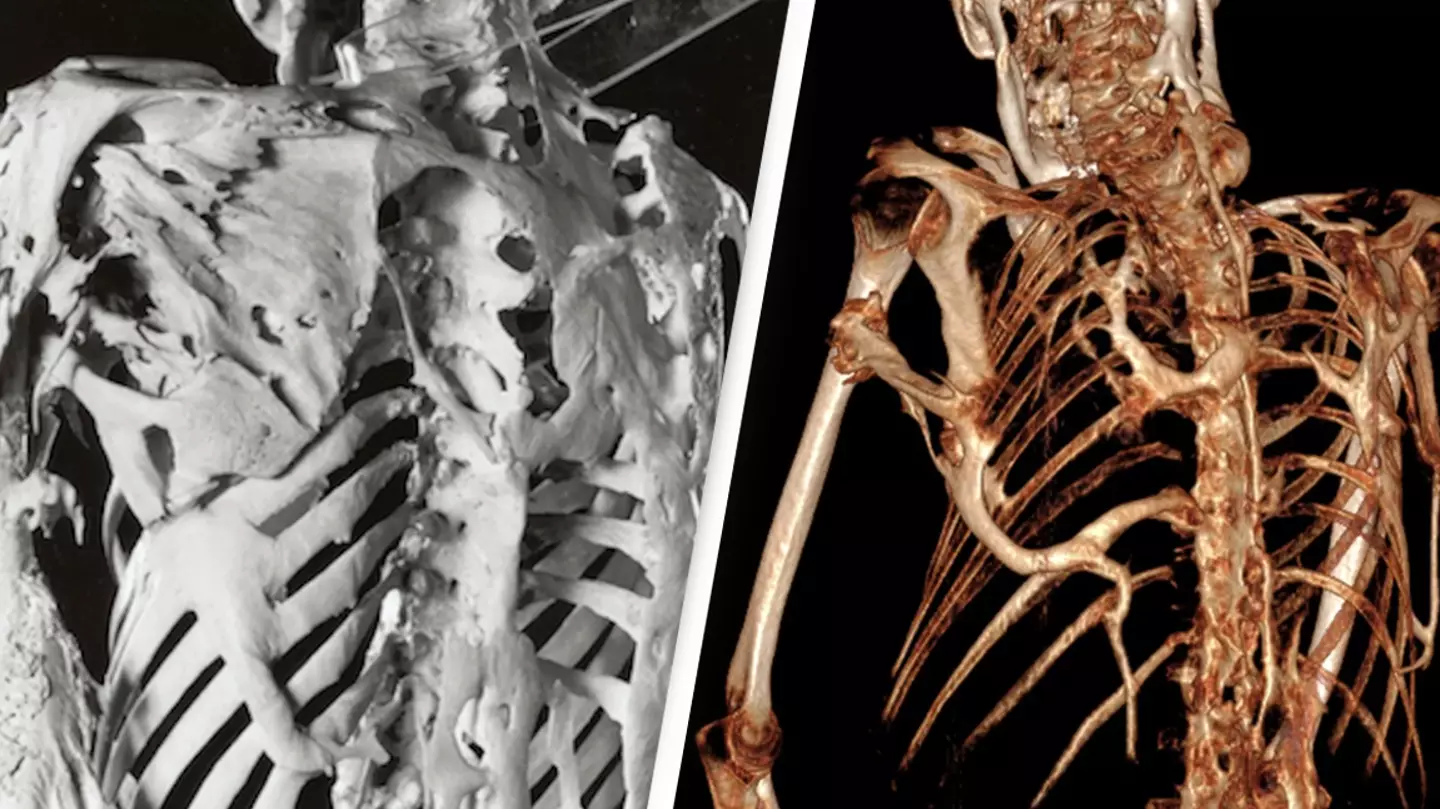

Known by its scientific name Fibrodysplasia ossificans progressiva (FOP), this musculoskeletal condition causes the muscles and tendons to transform into bone through a process known as Ossification. It's said to create a second 'skeleton' of extra bone around the muscles and other organs.

X-ray photos show just how uncomfortable this disease must be as sharp, jagged bones encase the person's entire body, more so in some places than in others.